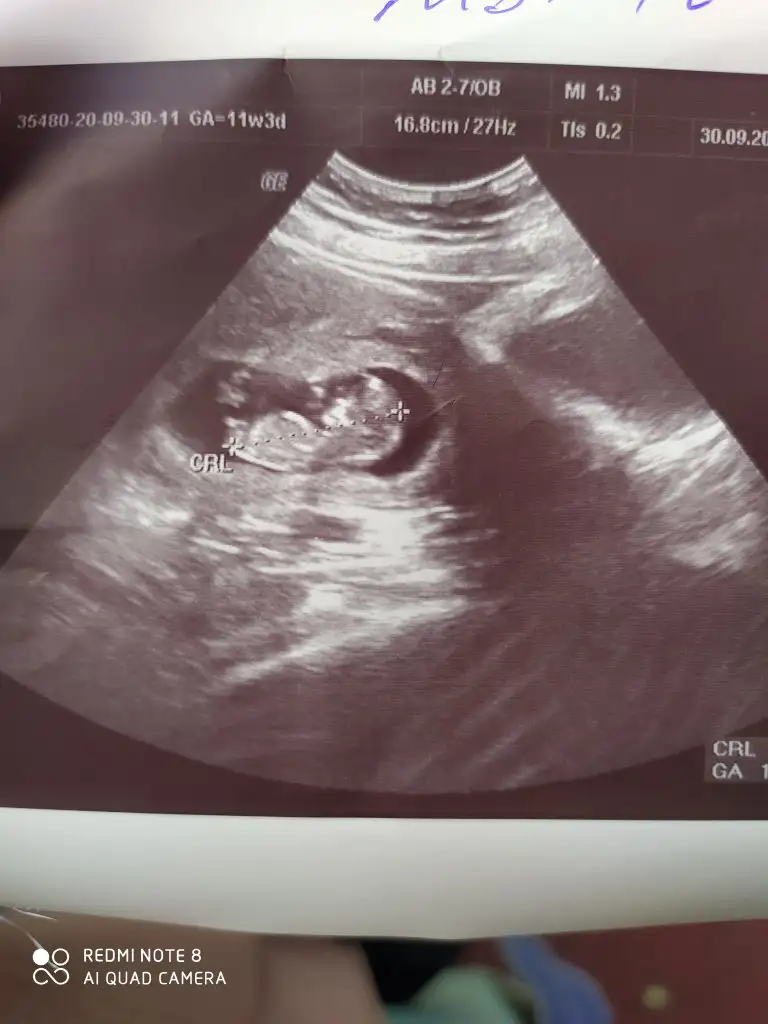

Benim bebeğim sizce ne? 7+1 ultrason 🥰